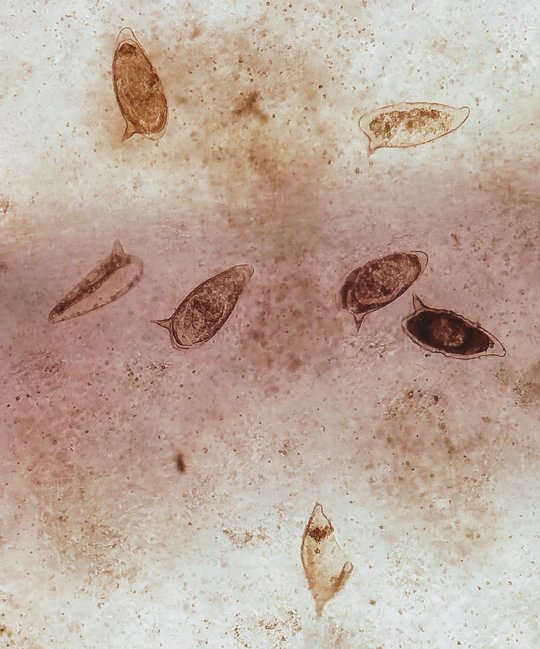

Die Identität absterbender Zellen, die von Fresszellen aufgenommen werden, beeinflusst die Funktion dieser phagozytierenden Makrophagen. Bei einer Infektion mit dem Parasiten Schistosoma mansoni setzen sich seine Eier in der Leber des infizierten Wirts fest. Es bilden sich Granulome um das Ei – dies sind Umbildungen in der Leber, die neben den Gewebezellen Immunzellen wie Makrophagen enthalten. Die Umgebung im Granulom ist mit dem anti-entzündlichen Molekül IL-4 (Interleukin-4) angereichert. Die Granulome reduzieren die durch das Ei im Wirt hervorgerufene Immunreaktion. Die Makrophagen und unterschiedliche absterbende Zellen wie apoptotische T-Zellen, apoptotische Leberzellen (Hepatozyten) sowie apoptotische Neutrophile (eine Art von Immunzellen) kommen im Granulom in unmittelbare Nähe zueinander vor.

Erstautorin Imke Liebold und ihre Kolleg:innen aus der Forschungsgruppe von Lidia Bosurgi führten die Laborarbeiten am BNITM durch. Sie entdeckten, dass Makrophagen bei der Aufnahme der sie umgebenden sterbenden Zellen unterschiedliche Profile annehmen, die von der zellulären Identität der aufgenommenen Zelle abhängen: Nehmen die Fresszellen absterbende Neutrophile auf, bilden sie ein gewebeumbauendes Profil aus, d.h., anschließend unterstützen sie hauptsächlich den Umbau des Gewebes. Eine wichtige Rolle spielen dabei die Rezeptoren AXL und MERTK der Makrophagen – die Forschenden konnten zeigen, dass die Makrophagen nicht das gewebeumbauende Profil annahmen, wenn die Rezeptoren experimentell ausgeschaltet waren. Nehmen die Makrophagen absterbende Leberzellen auf, nehmen sie anschließend immunsuppressive Aufgaben wahr. Nehmen die Makrophagen hingegen absterbende T-Zellen auf, bilden sie daraufhin kein spezielles Profil aus.